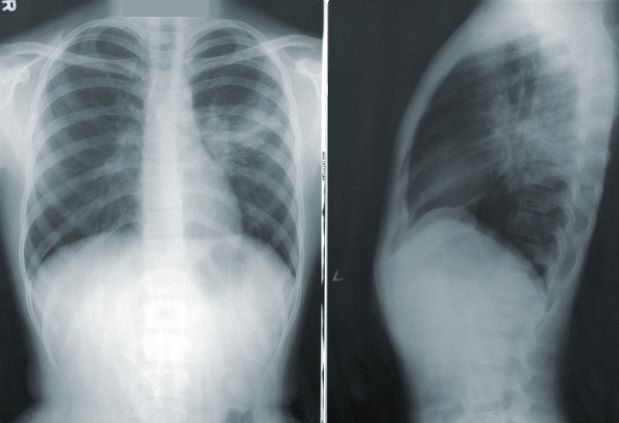

폐렴의 진단은 폐렴 주요 증상과 함게 호흡음, 발열 등의 진찰 소견과 함께 X-ray 촬영에서 폐 조직 내 고름이 많이 축적된 모습이 발견되면 폐렴으로 진단합니다.